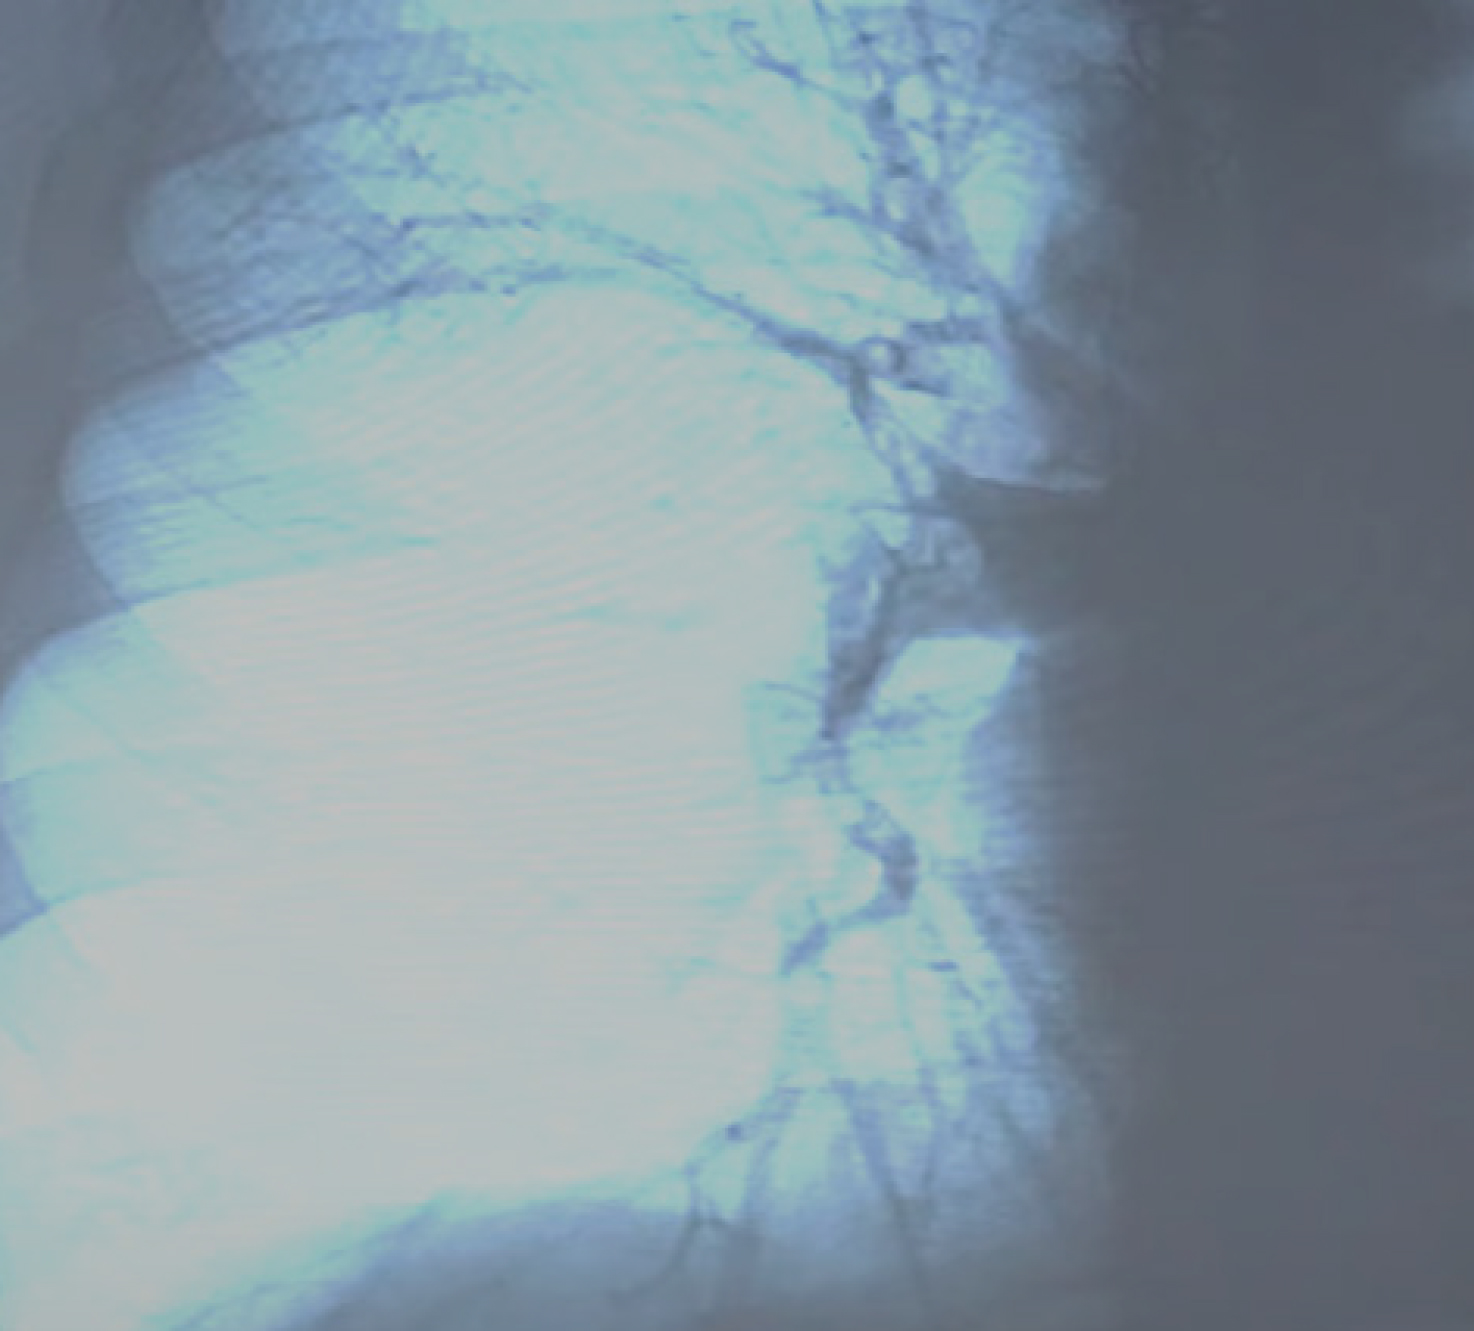

При осмотре нижних конечностей выявлены варикозные изменения поверхностных вен. Пациентке проведено ультразвуковое исследование вен нижних конечностей. В глубокой вене бедра выявлен флотирующий тромб (рис. 1 а), поверхностные вены расширены (рис. 1 б), кровоток в коммуникантах инверсирован.

а б Рис. 1. Данные УЗИ вен нижних конечностей. Флотирующий тромб в системе глубокой бедренной вены: а – варикозно расширенные поверхностные вены нижней конечности; б – источник ТЭЛА, глубокая венозная система ноги (пристеночная часть тромба, оставшаяся после случившейся эмболии)